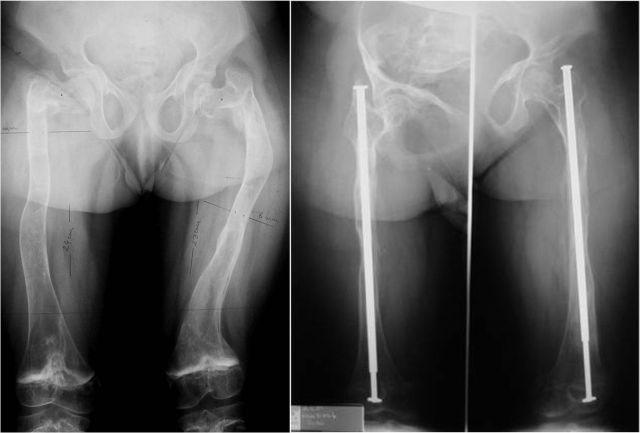

In the above-mentioned period, from the OI patients who are in the evidence of our clinic, 32 were operated on, totaling 81 surgeries. Out of these, 28 patients, aged 2-27 years, have benefited from reconstructive surgery of the pelvic limbs. Sofield-Millar osteotomies were practiced and 69 Sheffield telescopic rods were implanted in 25 patients and 43 surgeries. The coxa vara / valga correction using the Sheffield rod was applied in 6 patients and 8 hips, respectively. Circular or monoplane external fixators were used in 7 patients for the correction of deformities, lengthening and arthrodiastasis. 9 patients have benefited from various forms of bone transplant: pedicled grafts, auto- and/or allografts. An original bone reconstruction procedure is currently being studied and will be useful in the treatment of large bone defects and the thickening of the gracile diaphyses, which consists in practice of a massive contribution of free bone grafts, auto- and/or allogenic, bone substitutes and, in selected cases, periosteal substitutes, in a composite stratified construction. Postoperatively, 15 patients are able to walk while being supported by crutches or walking frames, 5 patients walk independently and 8 are still wheelchair-bound. It is important to mention that 8 children who were preoperatively dependant on the wheelchair are now walking!

在上述期间,在我们诊所登记的OI患者中,有32人接受了手术,共计81次手术。其中,28名年龄在2至27岁的患者接受了骨盆四肢的重建手术。实施了索菲尔德 - 米勒截骨术,并在25名患者的43次手术中植入了69根谢菲尔德伸缩杆。分别对6名患者的8个髋关节应用谢菲尔德杆进行了髋内翻/髋外翻矫正。7名患者使用环形或单平面外固定器进行畸形矫正、肢体延长和关节扩张。9名患者接受了各种形式的骨移植:带蒂移植、自体和/或异体移植。目前正在研究一种原始的骨重建程序,该程序将有助于治疗大的骨缺损和纤细骨干的增厚,其实际操作是大量使用游离骨移植、自体和/或异体骨替代物,以及在特定情况下使用骨膜替代物,进行复合分层构建。术后,15名患者能够借助拐杖或助行架行走,5名患者能够独立行走,8名患者仍需依赖轮椅。需要提及的是,8名术前依赖轮椅的儿童现在能够行走了!